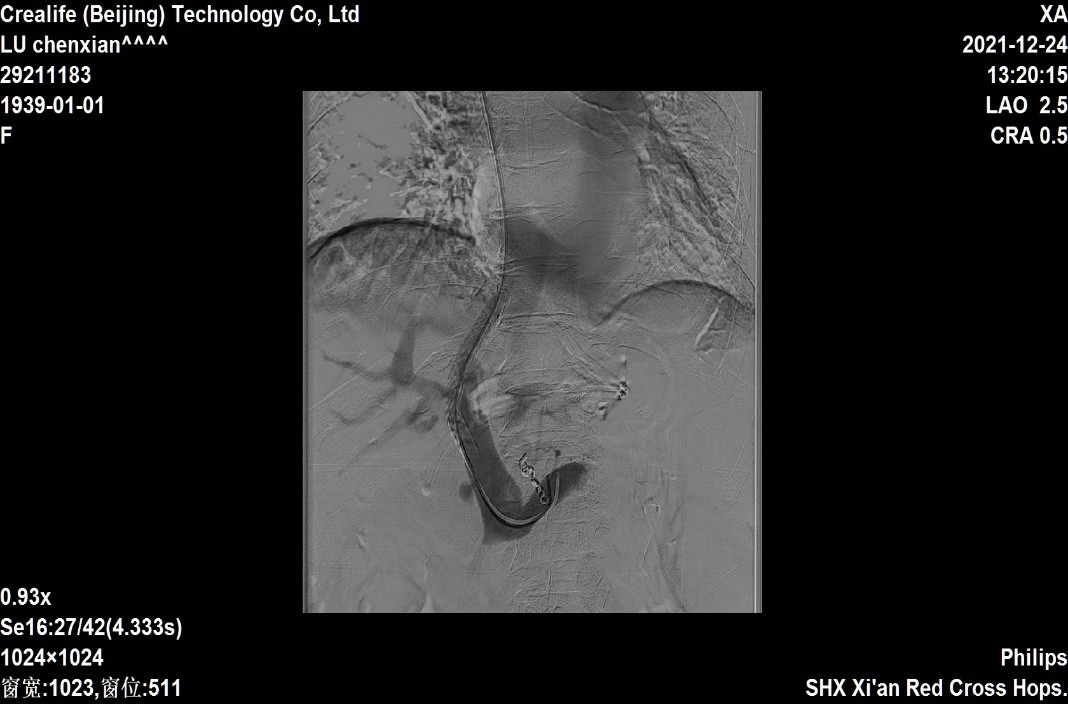

A图门静脉造影,可见食管胃底静脉曲张;B图支架释放后血管造影;C图弹簧圈栓塞静脉曲张出血血管;D图支架植入曲张血管栓塞后造影出血血管消失,支架血流通畅

完善术前准备后,由消化内科余天垒医师顺利完成手术。手术过程包括了穿刺、造影、测压、球囊扩张、支架置入、血管栓塞等多项技术操作,其中在透视下由肝静脉向门静脉穿刺尤为困难,余天垒医师凭借丰富的介入手术经验,成功穿刺,分压止血。术后第2天,患者即恢复正常饮食,现患者恢复即将出院。